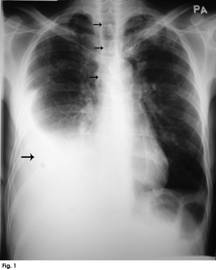

A chest radiograph, PA view, was done. On viewing, the chest radiograph appeared to be fairly well-centralised. It showed the presence of a moderately large pleural effusion on the right side (Figure 1, single large black arrow) with lateral upward sloping of a meniscus-shaped contour. The fluid obliterated the right hemi-diaphragmatic contour. The trachea was also slightly deviated to the right side (Figure 1, small black arrows). It appeared to be a moderately large pleural effusion as the fluid occupied between 25-50% of the hemithorax.1 When the consultant physician saw the patient, a discussion ensued regarding the conflicting position of the trachea and lower mediastinum (heart), vis-à-vis the pleural effusion.

Figure 1: Chest radiograph of a patient with a right-sided pleural effusion. The pleural fluid is seen as opacity (single large black arrow) with lateral upward sloping of a meniscus-shaped contour. The right diaphragmatic contour is also completely obliterated, indicating presence of fluid in the right pleural space. In spite of a moderately large right pleural effusion, the trachea appears to be slightly shifted to the right side (as depicted by small black arrows), and the heart also does not appear to be shifted to the left side, thereby indicating an underlying lung pathology on the right side. A right lower lobe collapse was subsequently diagnosed on high resolution computed tomography (HRCT) chest scan, as a consequence of right lung carcinoma.